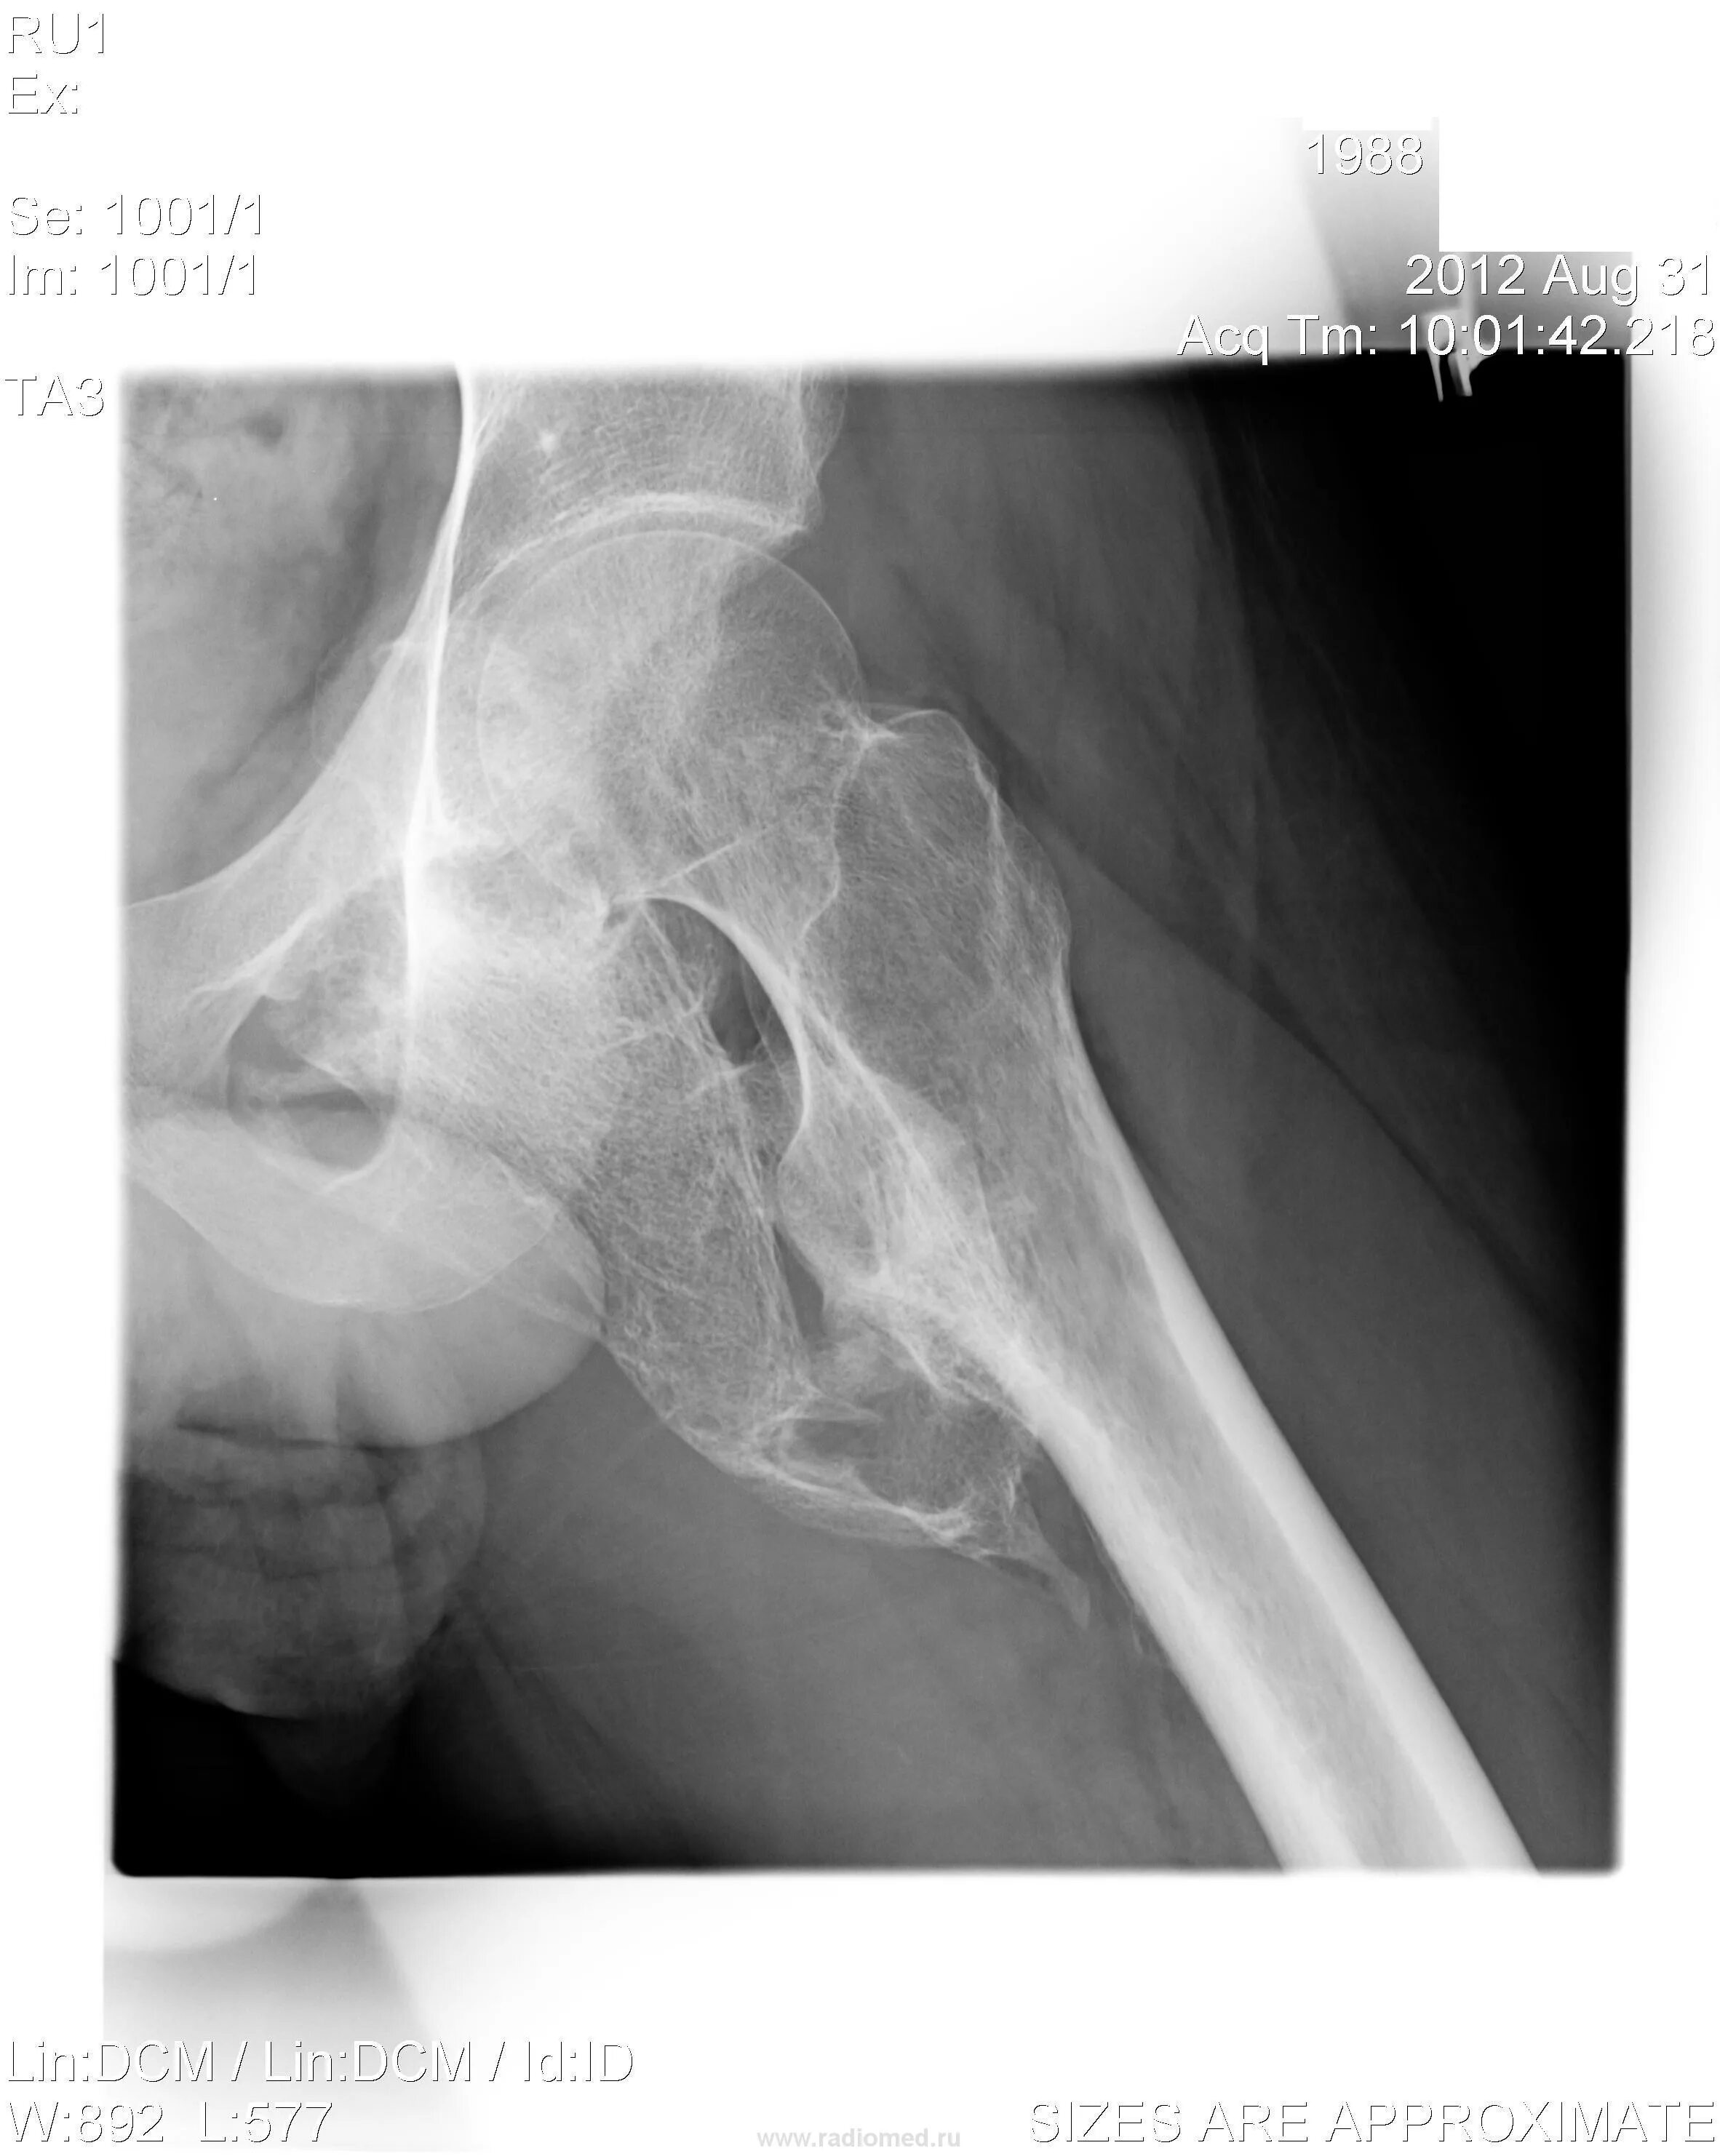

Оссифицированный миозит